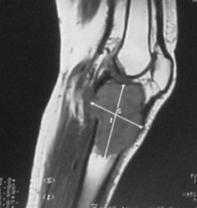

Grafidelezyonun çeperi (korteks) yumurta kabuğu görünümündedir. Düz grafide sabun köpüğü manzarasıtipiktir. Anevrizmal kemik kistinin genişliği metafizden fazladır. Basit kemik kistinin genişliği yakın olan fizden daha büyük değildir. Anevrizmal kemik kisti ile basit kemik kistinin ayırıcı tanısında, MRI’da sıvı-sıvı seviyesi tanı koydurmada yardımcıdır.

Tedavide küretaj+greftleme veya eksizyon uygulanır. Küretajdan sonra kriyoterapi veya kimyasal koterizasyon uygulanabilir, takiben grefonaj yapılır. Lokal nüks oranı %15-20’dir. 15 yaşından genç hastalarda nüks oranı yüksektir. Ameliyat öncesi yapılacak embolizasyon kanama miktarını azaltır. Anevrizmal kemik kistinde biyopsi yapılmasında yarar vardır.